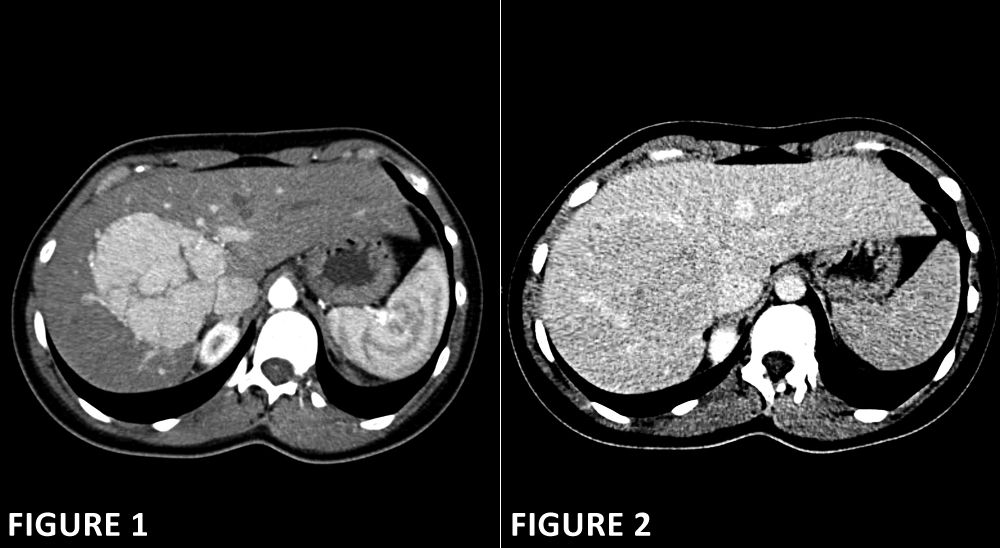

A 28-year-old woman with a history of nephrolithiasis has an abdomen CT scan to investigate an abnormality in the liver detected on a prior non-contrast CT performed in the emergency department. She has no other medical issues. Axial images from a contrast-enhanced CT scan are shown below (Figure 1 arterial and Figure 2 delayed phases).

What is your diagnosis?